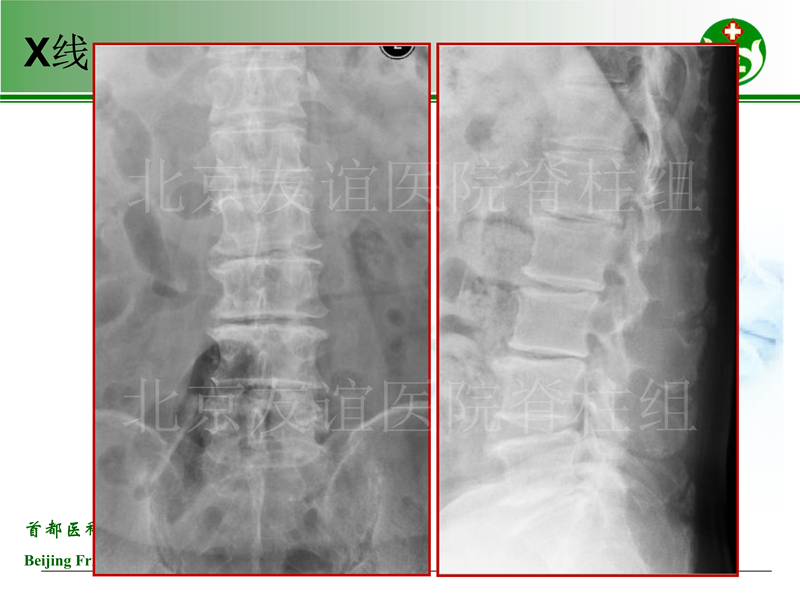

影像片:

男性,73岁,VAS6(腰4,双下肢6)

主诉:腰痛2年,加重伴间歇性跛行3个月,小于50米

既往史:高血压病

查体:下腰部及椎旁压痛(+),下肢抬高试验40度(+)